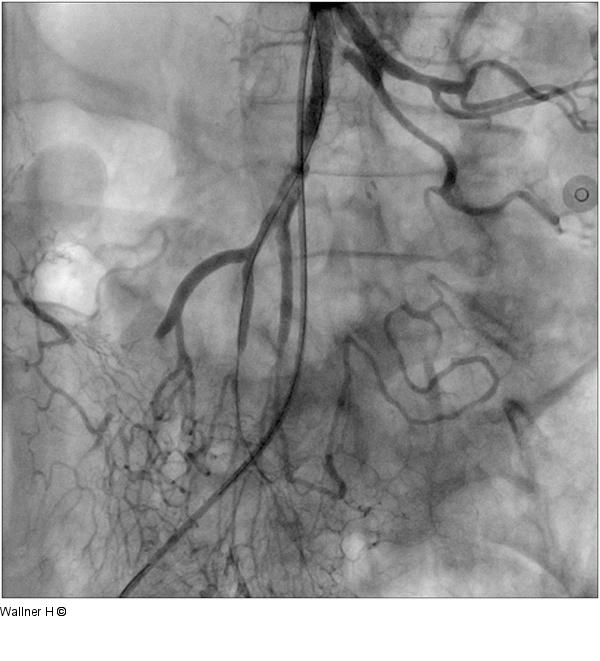

Abbildung 4: Zweifachstentimplantation Wiedereröffneter Hauptstamm mit Zweifachstentimplantation, Auffüllung der Arkadengefäße, peripher noch embolisch bedingter Verschluss eines Hauptgefäßes |

Wiedereröffneter Hauptstamm mit Zweifachstentimplantation, Auffüllung der Arkadengefäße, peripher noch embolisch bedingter Verschluss eines Hauptgefäßes |